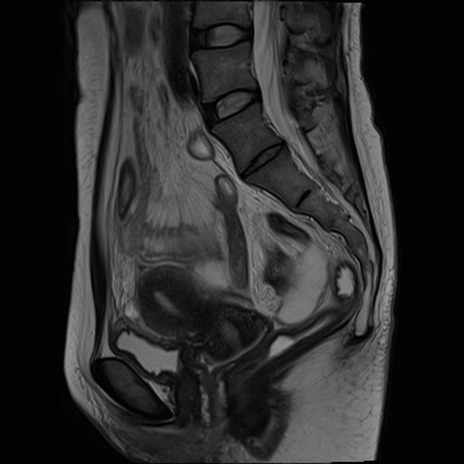

症例39 T2WI(矢状断像)

MRI(4日後)